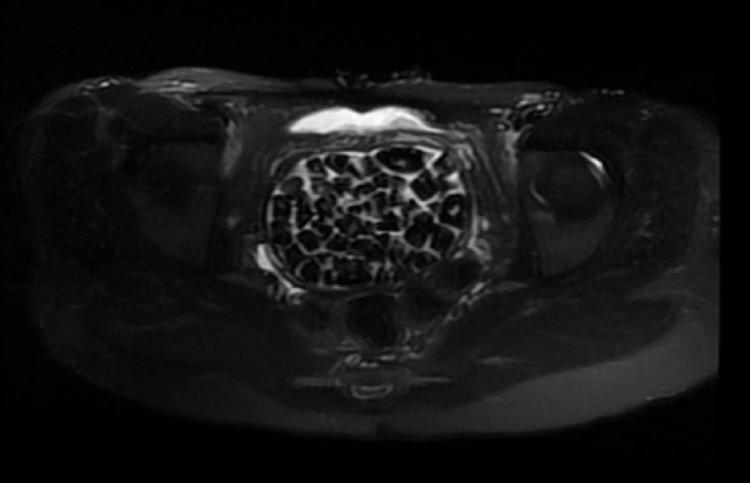

Taşlar hem sağlık ekibini hem hasta ve ailesini şok ederken uzmanlar, "Mesaneden vajene geçtiğimiz esnada tüm vajenin taşlarla dolu olduğunu gördük. Biz de o kadar taş beklemiyorduk, çok şaşırdık, en büyüğü 2,5 santim boyutlarında olan irili ufaklı 287 taş. Literatürde çok nadir görülen bir olay" açıklamasını yaptı.